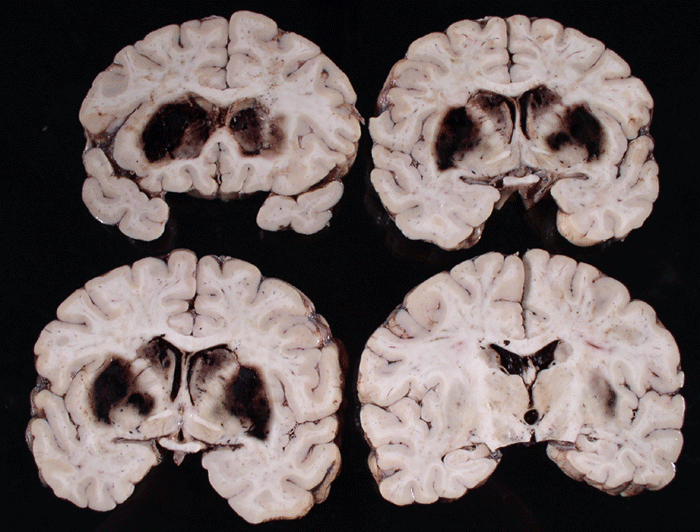

Gross neuropathologic findings: The brain weighs 1575 grams and is swollen but remains symmetrical. The sulci are largely flattened by the edema. The cerebral hemispheres and cerebellum have overall dusky discoloration. There was no evidence of cingulate, tonsillar, or uncal herniation. The vessels are patent and show minimal amounts of atherosclerosis.

On coronal sections, bilateral putamen and globus pallidus are hemorrhagic and contain large blood clots. Both caudate nuclei are also soft and hemorrhagic with small amount of blood rupturing into the lateral venticles with extension to the third and fourth ventricles. Despite the ventricular blood, there is no ventricular enlargement. In fact, the lateral ventricles appear compressed because of the cerebral edema. The fourth ventricle is slightly dilated by the intraventricular hemorrhage. Overall, there is a striking symmetry between the hemorrhage on the left side and the right side. Also, the hemorrhages in the caudate nuclei appear to be separate foci rather then extension of the hemorrhage from the putamen. Despite the close proximity of the internal capsules and thalamus to the hemorrhagic basal ganglia, they appear uninvolved. The cerebral cortex, cerebral penducle, the corpus callosum, and centrum ovale are within normal limits. The cerebellum and brain stem are also grossly unremarkable. The symetrical distribution and hemorrhage limited to the caudate, putamen and globus pallidus is quite unusual in this case.